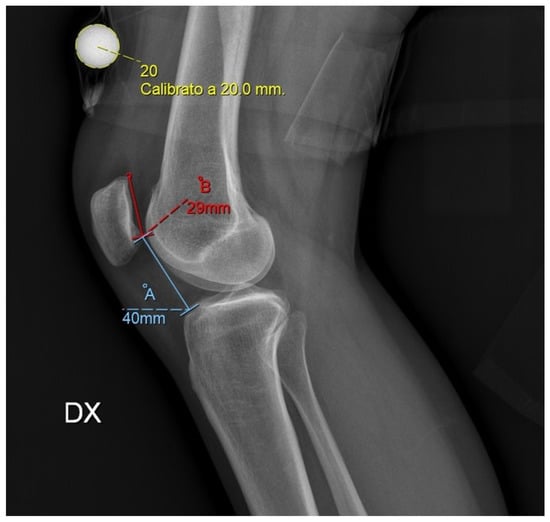

Depending on TT-TG and CDI, different surgical techniques were chosen. In case of patellar instability with normal TT-TG (<16 mm) and normal CDI (<1.2), only MPFL reconstruction was performed. When TT-TG was pathologic and CDI was normal, ATA medialization osteotomy was performed. When CDI was pathologic and TT-GT was normal, ATA lowering osteotomy was preferred. When both TT-TG and CDI were altered, a medialization and lowering osteotomy was performed. The patellar lowering necessary to achieve a normal CDI was calculated in millimeters, starting from the preoperative CDI measured on lateral radiographs with a 20 mm calibration marker (Figure 1).

Figure 1.

Caton–Deschamps index (CDI) assessed in a preoperative radiography of the knee, lateral view. In this example, CDI corresponds to 1.38, being = , which means patella alta. Knowing that CDI should not be more than 1.2, using the proportion B x 1.2, we obtained the value B′ (29 × 1.2 = 34.8 mm) which corresponds to the maximum hypothetical length of A so that the patella does not result high. Then, with a simple subtraction, B − B′ = 40 − 34.8 = 5.2 mm, we calculated the distance of which we want to lower the bony brat during surgery. A 20 mm calibration marker is essential for making the correct lowering calculations.